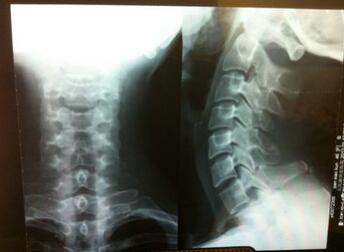

接诊的是王怀庆主任,根据李先生的检查报告制定了适合他自己的治疗方案。第一次治疗后,李先生说睡觉也舒服了,以前睡觉一翻身就疼醒,从腰到后背很不舒服,以前从来没有舒舒服服的睡过一次觉,治疗后感觉睡...[详细]